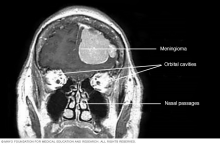

Computerized tomography (CT) scan showing a meningioma

Meningioma

This contrast-enhanced MRI scan of a person's head shows a meningioma. This meningioma has grown large enough to push down into the brain tissue.

• Meningiomas. Meningiomas are brain tumors that start in the membranes around the brain and spinal cord. Meningiomas are usually benign, but sometimes they can be malignant. Meningiomas are the most common type of benign brain tumor.